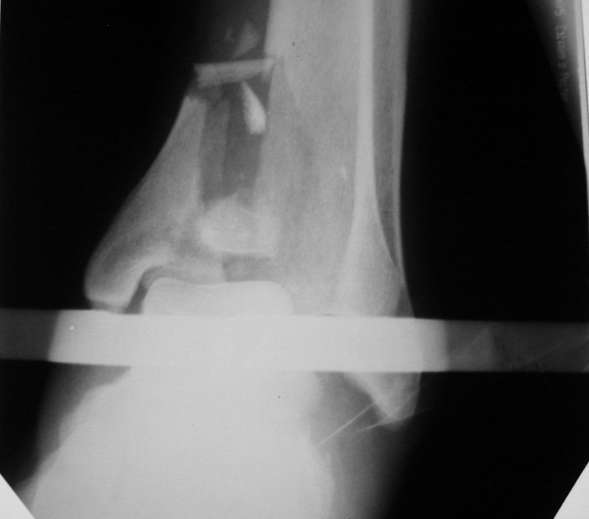

Мной был демонтирован АВФ, удалены все спицы. Больной некоторое время лечился консервативно (шина Белера, антибиотики, перевязки). По заживлению и купировании гнойно-воспалительного процесса была произведена осткрытая репозиция, накостный остеосинтез 1/3 трубчатой пластиной.Такой вариант был принят из-за жуткого остеопороза и отказом больного от предложенного артродезирования голеностопного сустава сразу. Послеоперационный период без особенностей. Через год, больной пришел на осмотр на своих двоих, без дополнительной опоры, с жалобами на боли приходьбе в обл. г/стопа и с желанием замкнуть сустав. В операционной столкнулся с неожиданной проблемой по удалению пластины, она была глубоко вмурована в толщу склерозированного метафиза на глубину 1.5 см; удалить не рискнул (считал, что металл помешает в ходе реконструкции и требуется его удаление).

Было решено, уже по ходу операции, выполнить артродез болтом-стяжкой, тем самым компрессируя резецированные суставные поверхности и смещая стопу латерально, дабы нивелировать варусную деформацию и восстанавливая тем самым опорную ось всей конечности.